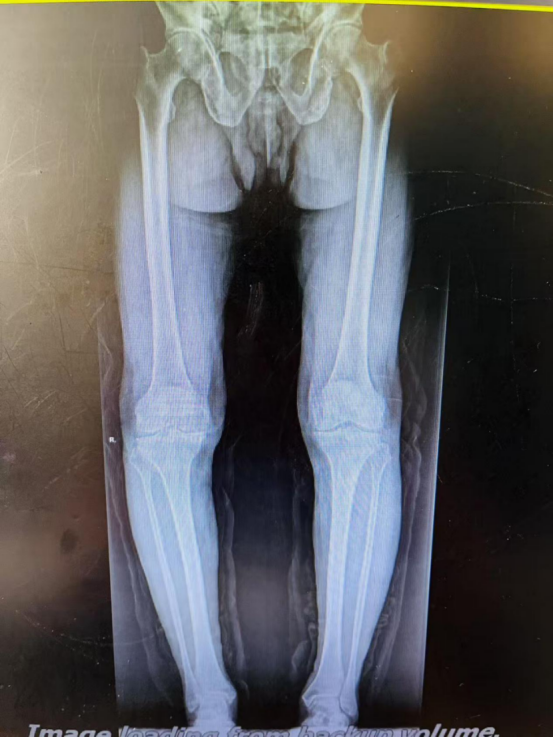

3月21日,富順縣人民醫(yī)院骨科中心收住一名87歲高齡的膝關(guān)節(jié)炎患者,患者被雙側(cè)膝關(guān)節(jié)炎病痛折磨近10年,嚴重影響患者日常生活,患者和家屬強烈要求行手術(shù)治療,改善膝關(guān)節(jié)功能。

雖然患者87歲高齡,手術(shù)風(fēng)險較大,但之前行膝關(guān)節(jié)保守治療,效果不佳,嚴重影響生活,患者及家屬手術(shù)意愿強烈,在完善相關(guān)輔助檢查后,考慮無絕對手術(shù)禁忌,骨科團隊決定為其實施手術(shù)。3月26日,由骨一科主任楊勇主刀,王波主治醫(yī)師及廖銳主治醫(yī)師協(xié)助,麻醉科全力配合下完成右側(cè)全膝關(guān)節(jié)置換手術(shù),手術(shù)順利,術(shù)后患者逐步恢復(fù)出院,出院前已能下地扶拐行走。